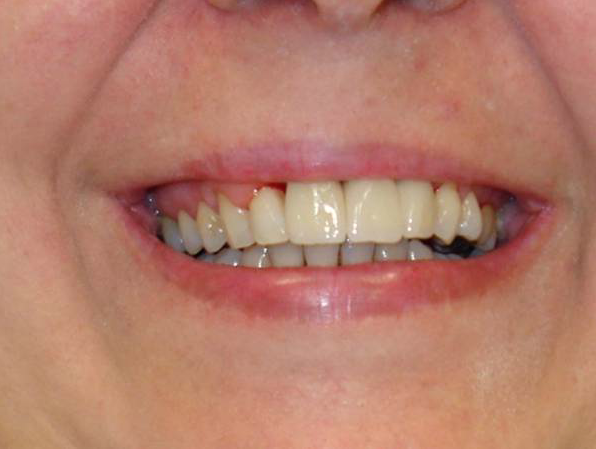

L'aumento globale dei problemi di edentulismo totale o parziale collegato all'aumento dell'età media nei paesi più sviluppati e non solo, come certificato dall'Organizzazione Mondiale della Sanità, mentre da un lato denota il fallimento almeno parziale delle metodiche preventive dall'altro porta ad un aumento della richiesta di sostituzione totale della dentatura compromessa. Tutto ciò si unisce, almeno nel mondo occidentale, a richieste di trattamenti pur invasivi ma rapidi e indolori.

Il più famoso trattamento di questo tipo è stato sviluppato dal Prof. Paulo Malo in collaborazione con la Nobel Biocare e prende il nome di

All-on-4®. Il trattamento in termini di risultato finale è analogo a uno dei trattamenti più innovativi della storia dell'implantologia osseointegrata, il cosiddetto "Toronto Bridge", che prende il nome dalla conferenza di Toronto del 1982 in cui il concetto del ponte fisso sostenuto da impianti osteointegrati ideato dal Prof. Per-Ingvar Brånemark dell'Universita di Göteborg per risolvere il problema dell'edentulismo mandibolare, osteggiato per anni dai colleghi di Brånemark stesso, fu introdotto finalmente con enorme successo al mondo accademico nordamericano dal Prof. Zarb dell'Università di Toronto. Ovviamente il trattamento moderno offre tutta una serie di vantaggi in termini di tempi, materiali e applicabilità della tecnica.

Un protocollo simile a quello dell'All-on-4® è quello proposto dal team del Prof. Pera con il Columbus Bridge Protocol, con innovazione soprattutto per quanto riguarda i materiali protesici. Il Columbus Bridge Protocol, così come l''All-on-4® sono protocolli con un'ampia documentazione scientifica alle spalle. Tutto questo dovrebbe portare ad una maggiore sicurezza per i pazienti.